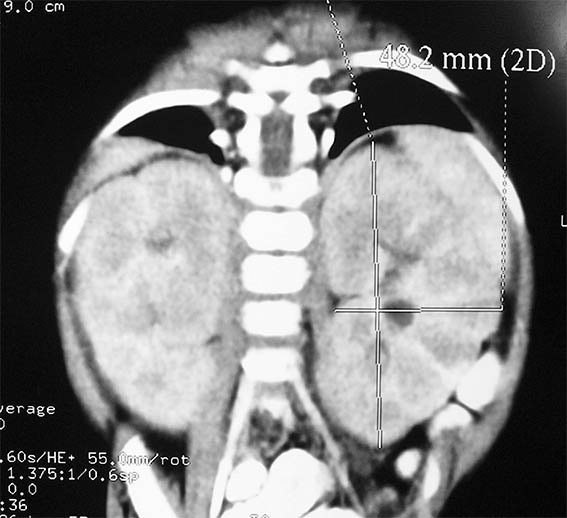

A five month-old girl presented with symptoms of malnutrition and severe urinary tract infection, with signs of sepsis and acute renal failure: serum creatinine 1.4 mg/dL. Both blood and urine cultures were positive for Escherichia coli, and antibiotic therapy was started. Severe, almost symmetrical, bilateral nephromegaly was evident on computed tomography (Figures 1 and 2). Voiding cystourethrography showed no urinary tract abnormalities.

Figure 1.